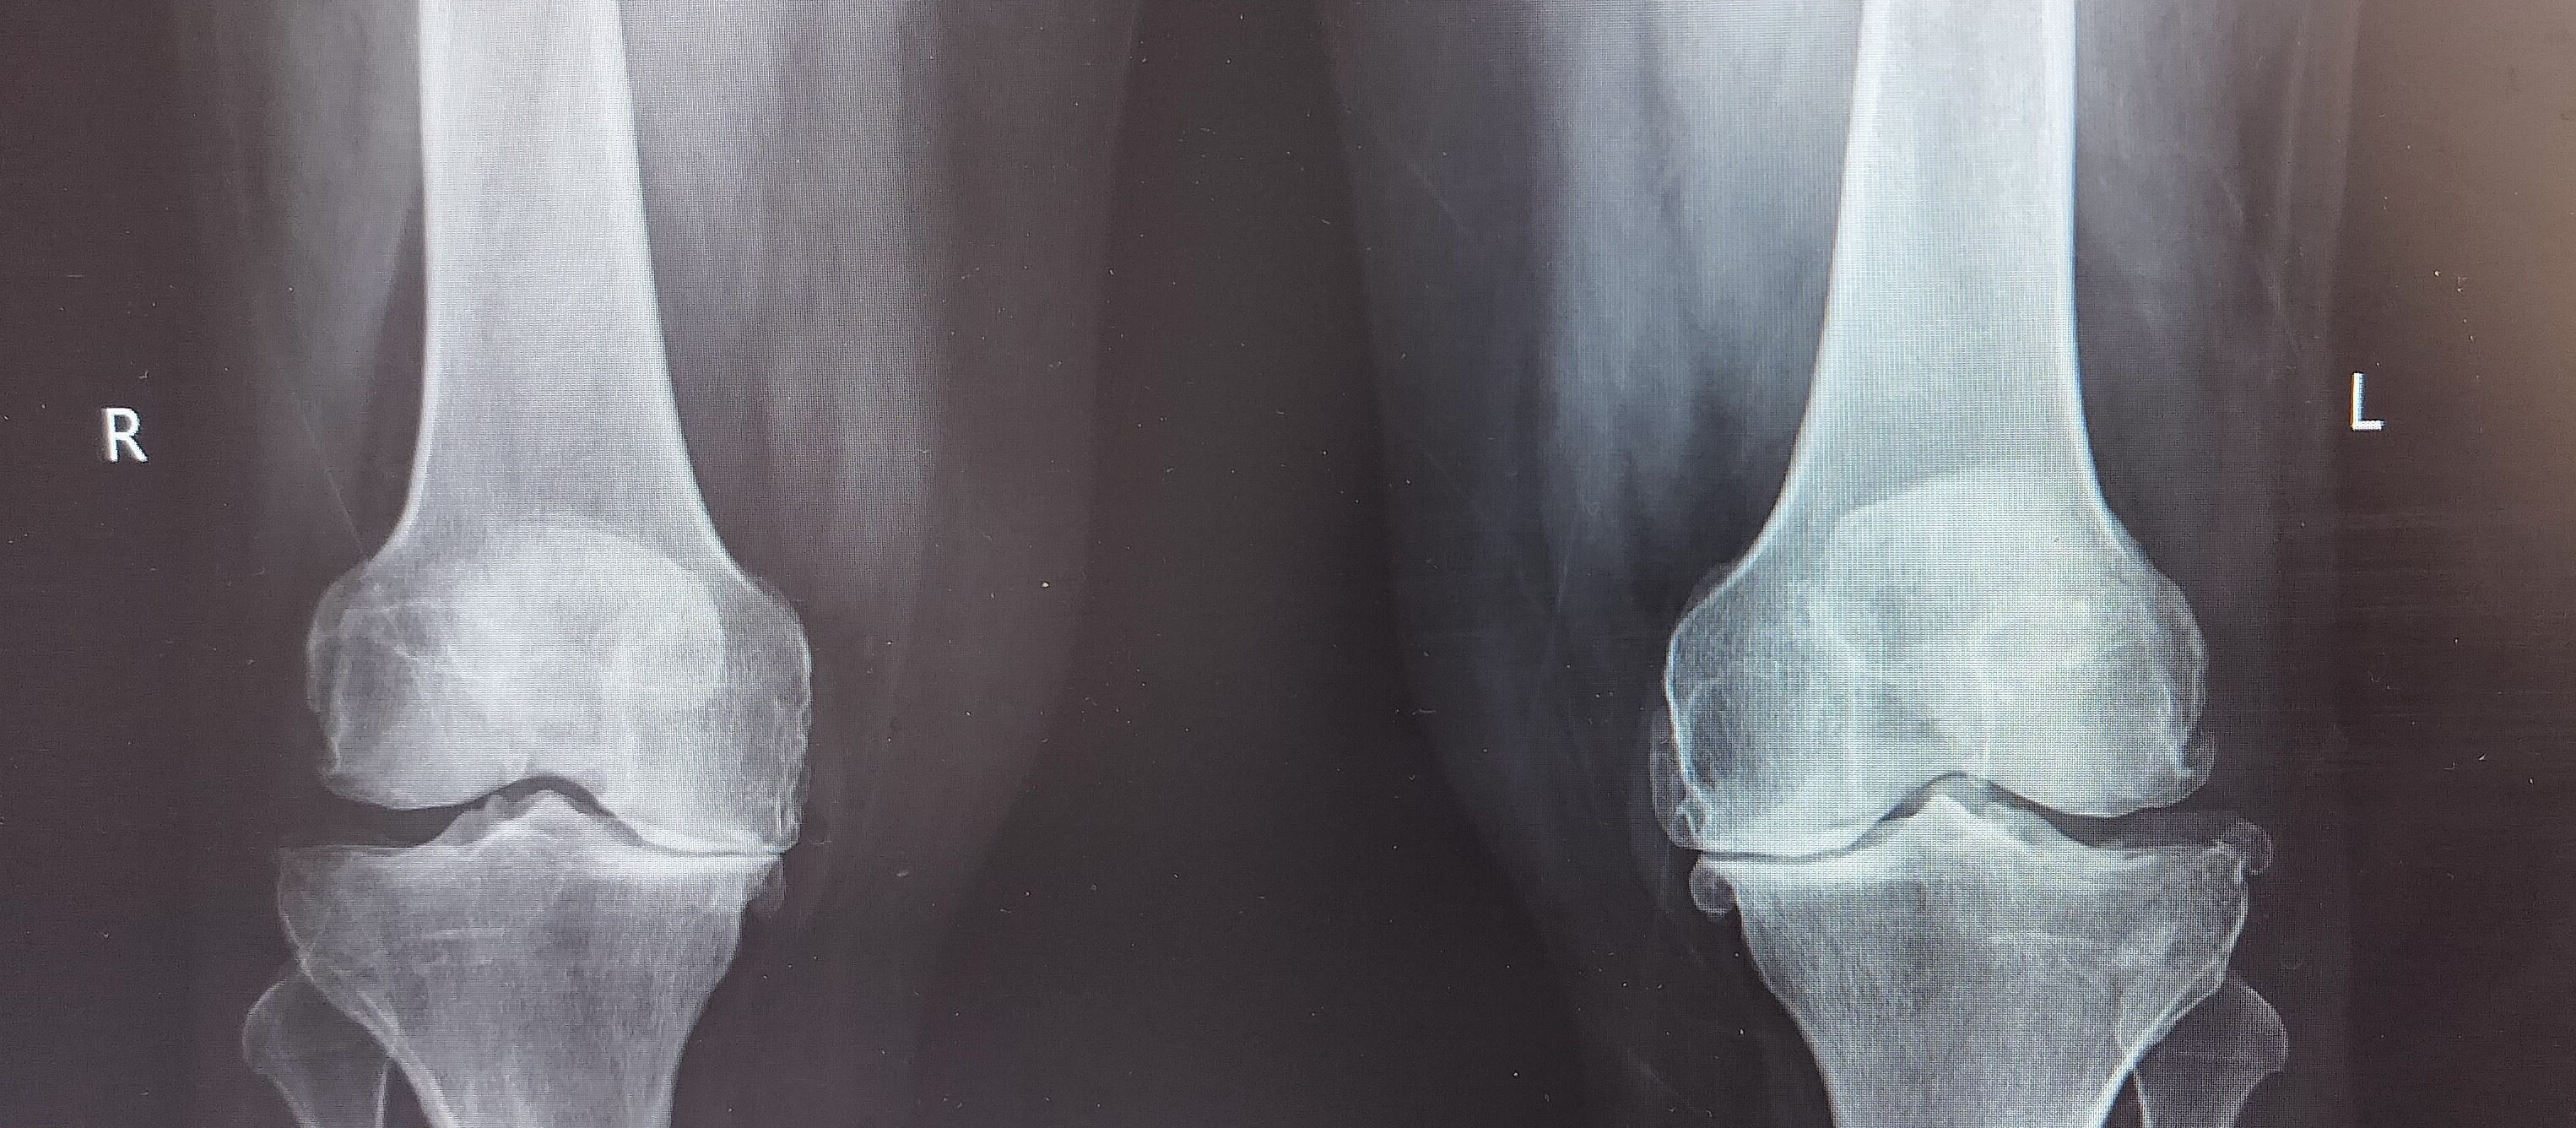

Meniscal repair

Repair of torn mensicus in the knee - Keyhole arthroscopic surgery

Senior Consultant Orthopaedic surgeon Dr. Kanniraj Marimuthu is a highly respected Orthopaedic Surgeon with expertise in joint replacement surgery, arthroscopic surgery, and sports injuries. With a career marked by international experience and academic excellence, he is committed to providing world-class care to his patients with compassion. Education & Early Career Dr. Kanniraj completed his MBBS from the prestigious Madras Medical College, Chennai, before pursuing his MS (Orthopaedics) at the renowned Sawai Man Singh Medical College in Jaipur. The institution is famous for developing the revolutionary "Jaipur Foot" for amputees. During his training, he was honoured with the All India Best Resident Orthopaedic Surgeon Award by the Bombay Orthopaedic Society in 2008 for his academic and clinical excellence. Career Highlights & Specializations • Senior Resident at All India Institute of Medical Sciences (AIIMS), New Delhi, specializing in joint replacement and arthroscopic surgery. • Awarded the First Prize for Research Paper by the Delhi Orthopaedic Association (DOACON 2011) for his work on Giant Cell Tumors of Bone. • Nominated by the Government of India for the prestigious Commonwealth Fellowship Program (2012-2013), for further clinical training in the UK. • Dr. Kanniraj then moved to Australia, where he completed fellowship training in joint replacement surgery, sports injuries, and arthroscopic surgery across Melbourne and Sydney, as part of an Australian Orthopaedic Association accredited program. • In November 2017, he was invited to Clinique Generale, Annecy, France, a pioneer center for shoulder surgery, to work with renowned shoulder surgeons Dr. Bruno Toussaint and Dr. Jerome Bahurel. Research & Contributions Dr. Kanniraj has published extensively in international orthopaedic journals and contributed chapters in prominent textbooks, including a chapter on Revision Hip Replacement in the "Textbook of Orthopaedics" by the Indian Orthopaedic Association. His expertise spans a wide range of orthopaedic conditions, with a particular focus on knee surgeries, joint replacement, and shoulder procedures. He brings a wealth of international experience, having trained in some of the world's leading institutions Philosophy & Patient Care Dr.Kanniraj’s approach to patient care is centred around achieving the best possible outcomes through a combination of personalized treatment plans, advanced surgical techniques, and a compassionate approach. He believes in involving patients in the decision-making process, ensuring that they are well-informed and comfortable at every stage of their treatment. His patient-first approach ensures that each individual receives the highest standard of care, from diagnosis to post-surgical rehabilitation.